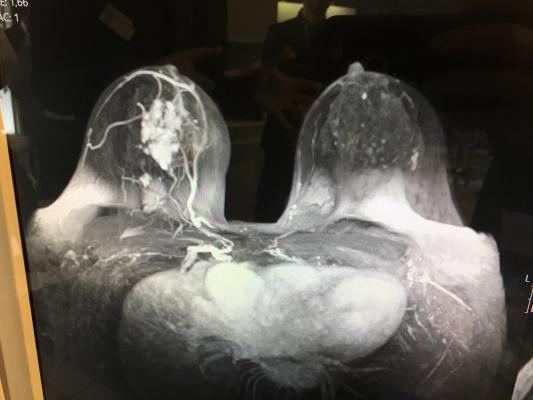

Breast Lesions Incidentally Detected With Ct What The General Radiologist Needs To Know Radiographics from pubs.rsna.org Definition purpose description preparation aftercare risks normal results. Breast cancer type and stage: Interventional radiologists, physicians who specialize in minimally before a pet/ct scan, an iv that injects a small amount of a radioactive substance will be placed into one of your veins. An mri scan of the breast may be. Medically reviewed by seunggu han, m.d. How many cancer deaths caused by unnecessary ct scan are occurring now? These techniques include ct scans, mri scans and radioisotope scans. Ct scanning is very valuable for diagnosing disease and also screening for certain health conditions in otherwise healthy people.

Your doctor might order ct scans to examine other parts of the body where breast cancer can spread, such as the lymph nodes, lungs, liver, brain, and/or spine.

Each has its own strengths. A ct scan can show whether breast cancer has spread to the lungs or liver. The lung cancer detection is the extension of the image processing that produces the results of feature extraction and feature selection after segmentation. Breast cancer type and stage: The image shows your bones, organs, and soft tissues more clearly. Monitor the effectiveness of certain. Ct scans and cat scans describe the same imaging test. A radiographer operates the scanner. You can have a ct scan done at the radiology or radiation oncology center of a hospital. This provides a series of images from many different angles. Medically reviewed by seunggu han, m.d. It's also important to follow recommended screening guidelines, which can help detect certain cancers early. If you have a condition like cancer, heart disease.